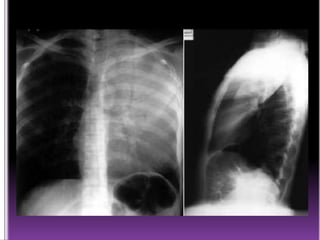

 Lesiones hipodensas del parénquima

pulmonar.

 Hiperclaridad circunscrita

 Forma, tamaño y contornos variables

 Nivel horizontal (liquido y gas en su interior)